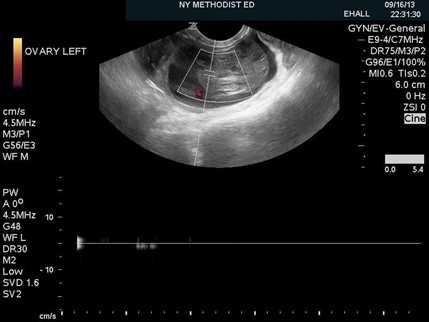

Figure 1. Ovarian torsion with absent flow